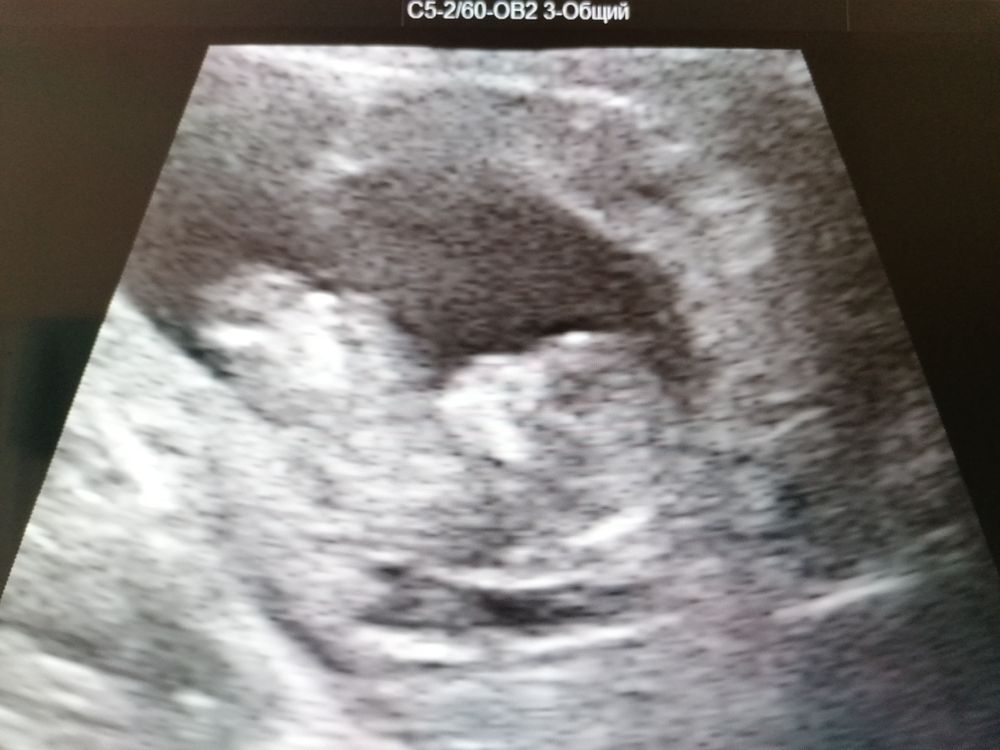

жду девочку, 14 неделя Ижевск

Первый скрининг